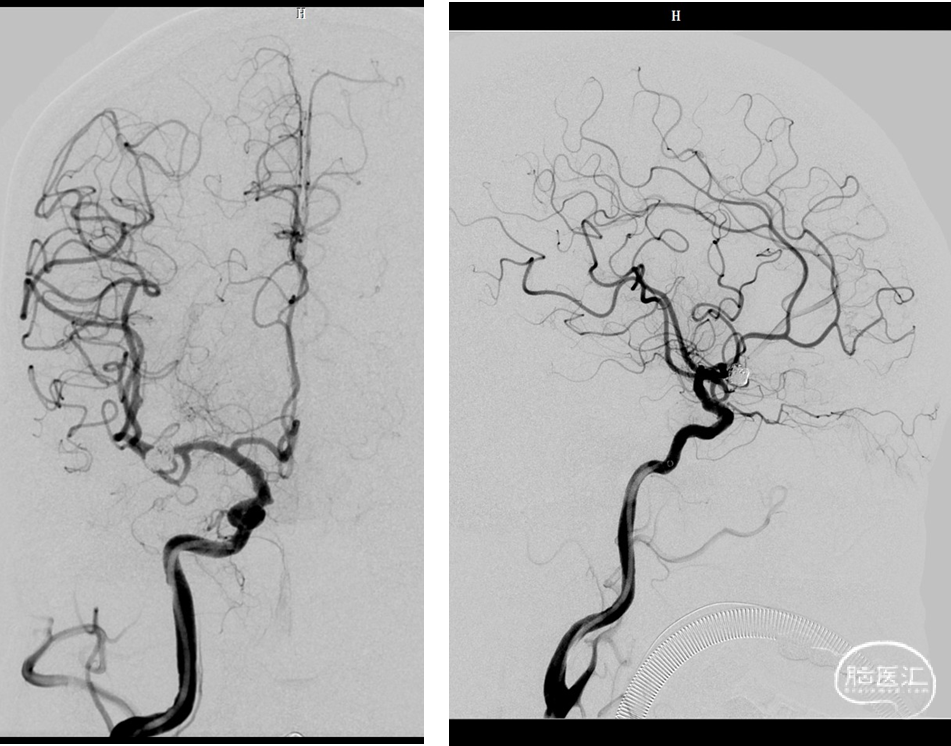

一般项目:患者女 年龄:71岁;

因“检查发现脑内动脉瘤10天”入院;

外院造影检查发现右侧大脑中动脉M1段动脉瘤、右侧颈内动脉眼动脉段动脉瘤。

⇨FD结合弹簧圈动脉瘤栓塞术

Lattice 2.6x18

泰杰 6mm*20cm 3D、 泰杰4.5mm*12cm 3D、 泰杰3mm*6cm 3D

原位释放,释放过程头端导丝无移位,无需推拉即可打开并贴壁:自动挡FD!